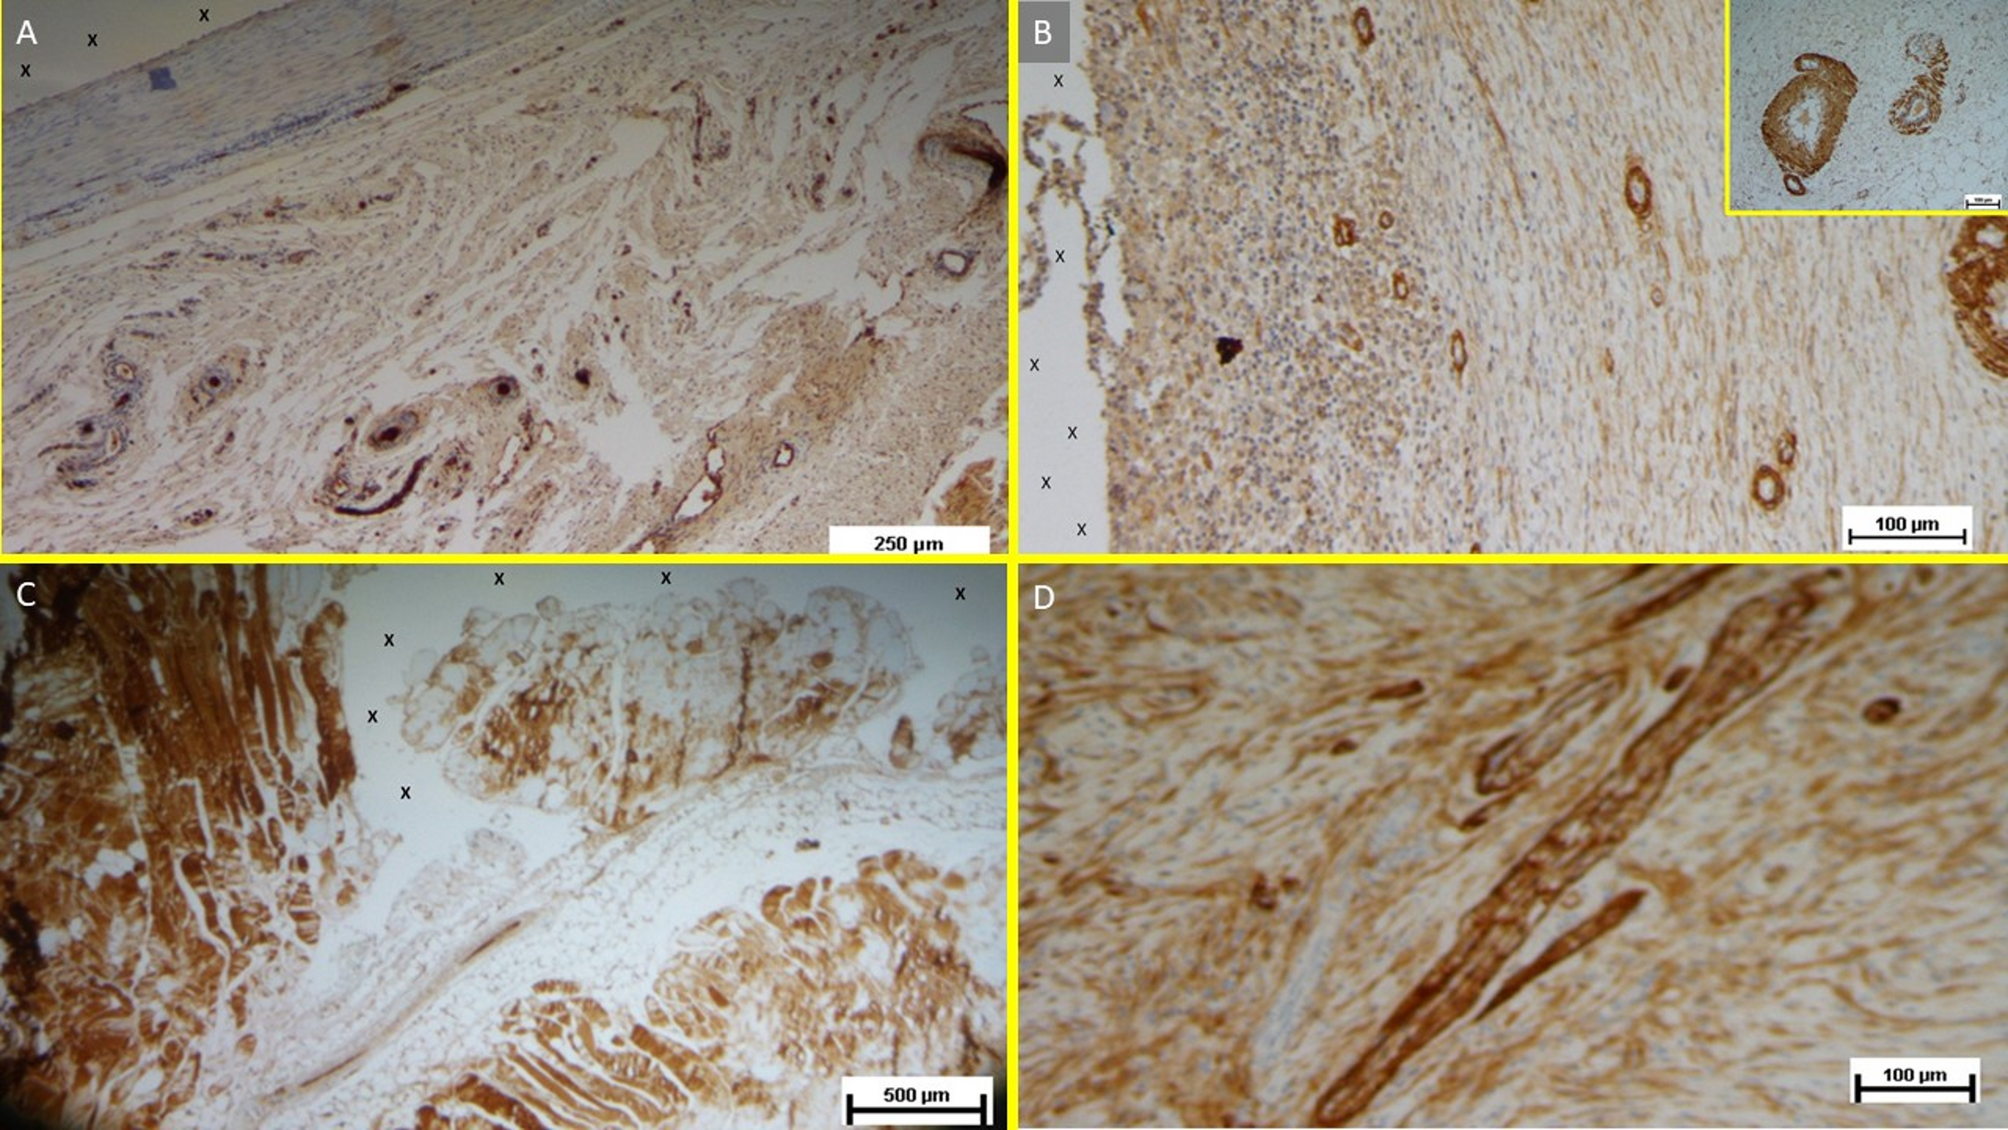

Fig. 12

(A) Tissue sample removed from the 3D scaffold of the S&D device six months implantation. Numerous clusters of intense neo-angiogenesis (colored in brown) with well-developed vascular structures are clearly evident close to the device fabric (X). CD31 50X—(B) Tissue sample excised from the 3D scaffold of the S&S device 8 months post-surgery. Numerous venous elements showing well-constituted muscular layer are highlighted close to the scaffold fabric (X). SMA 100X—The high magnification microphotograph in the right upper corner depicts two arterial structures with a well-represented muscular layer (colored in brown). SMA 200X—(C) Biopsy sample excised from the scaffold of the S&S device 6 months post implantation. The image shows plenty of muscular elements (colored in brown) grouped in bundles close to the TPE structure of the device. NGF 25X—(D) Biopsy specimen excised from the 3D scaffold of the S&S device 6 months post-implantation. The image shows a mature elongated nervous structure (colored in brown) developed within the TPE scaffold. NGFRp75 100X.